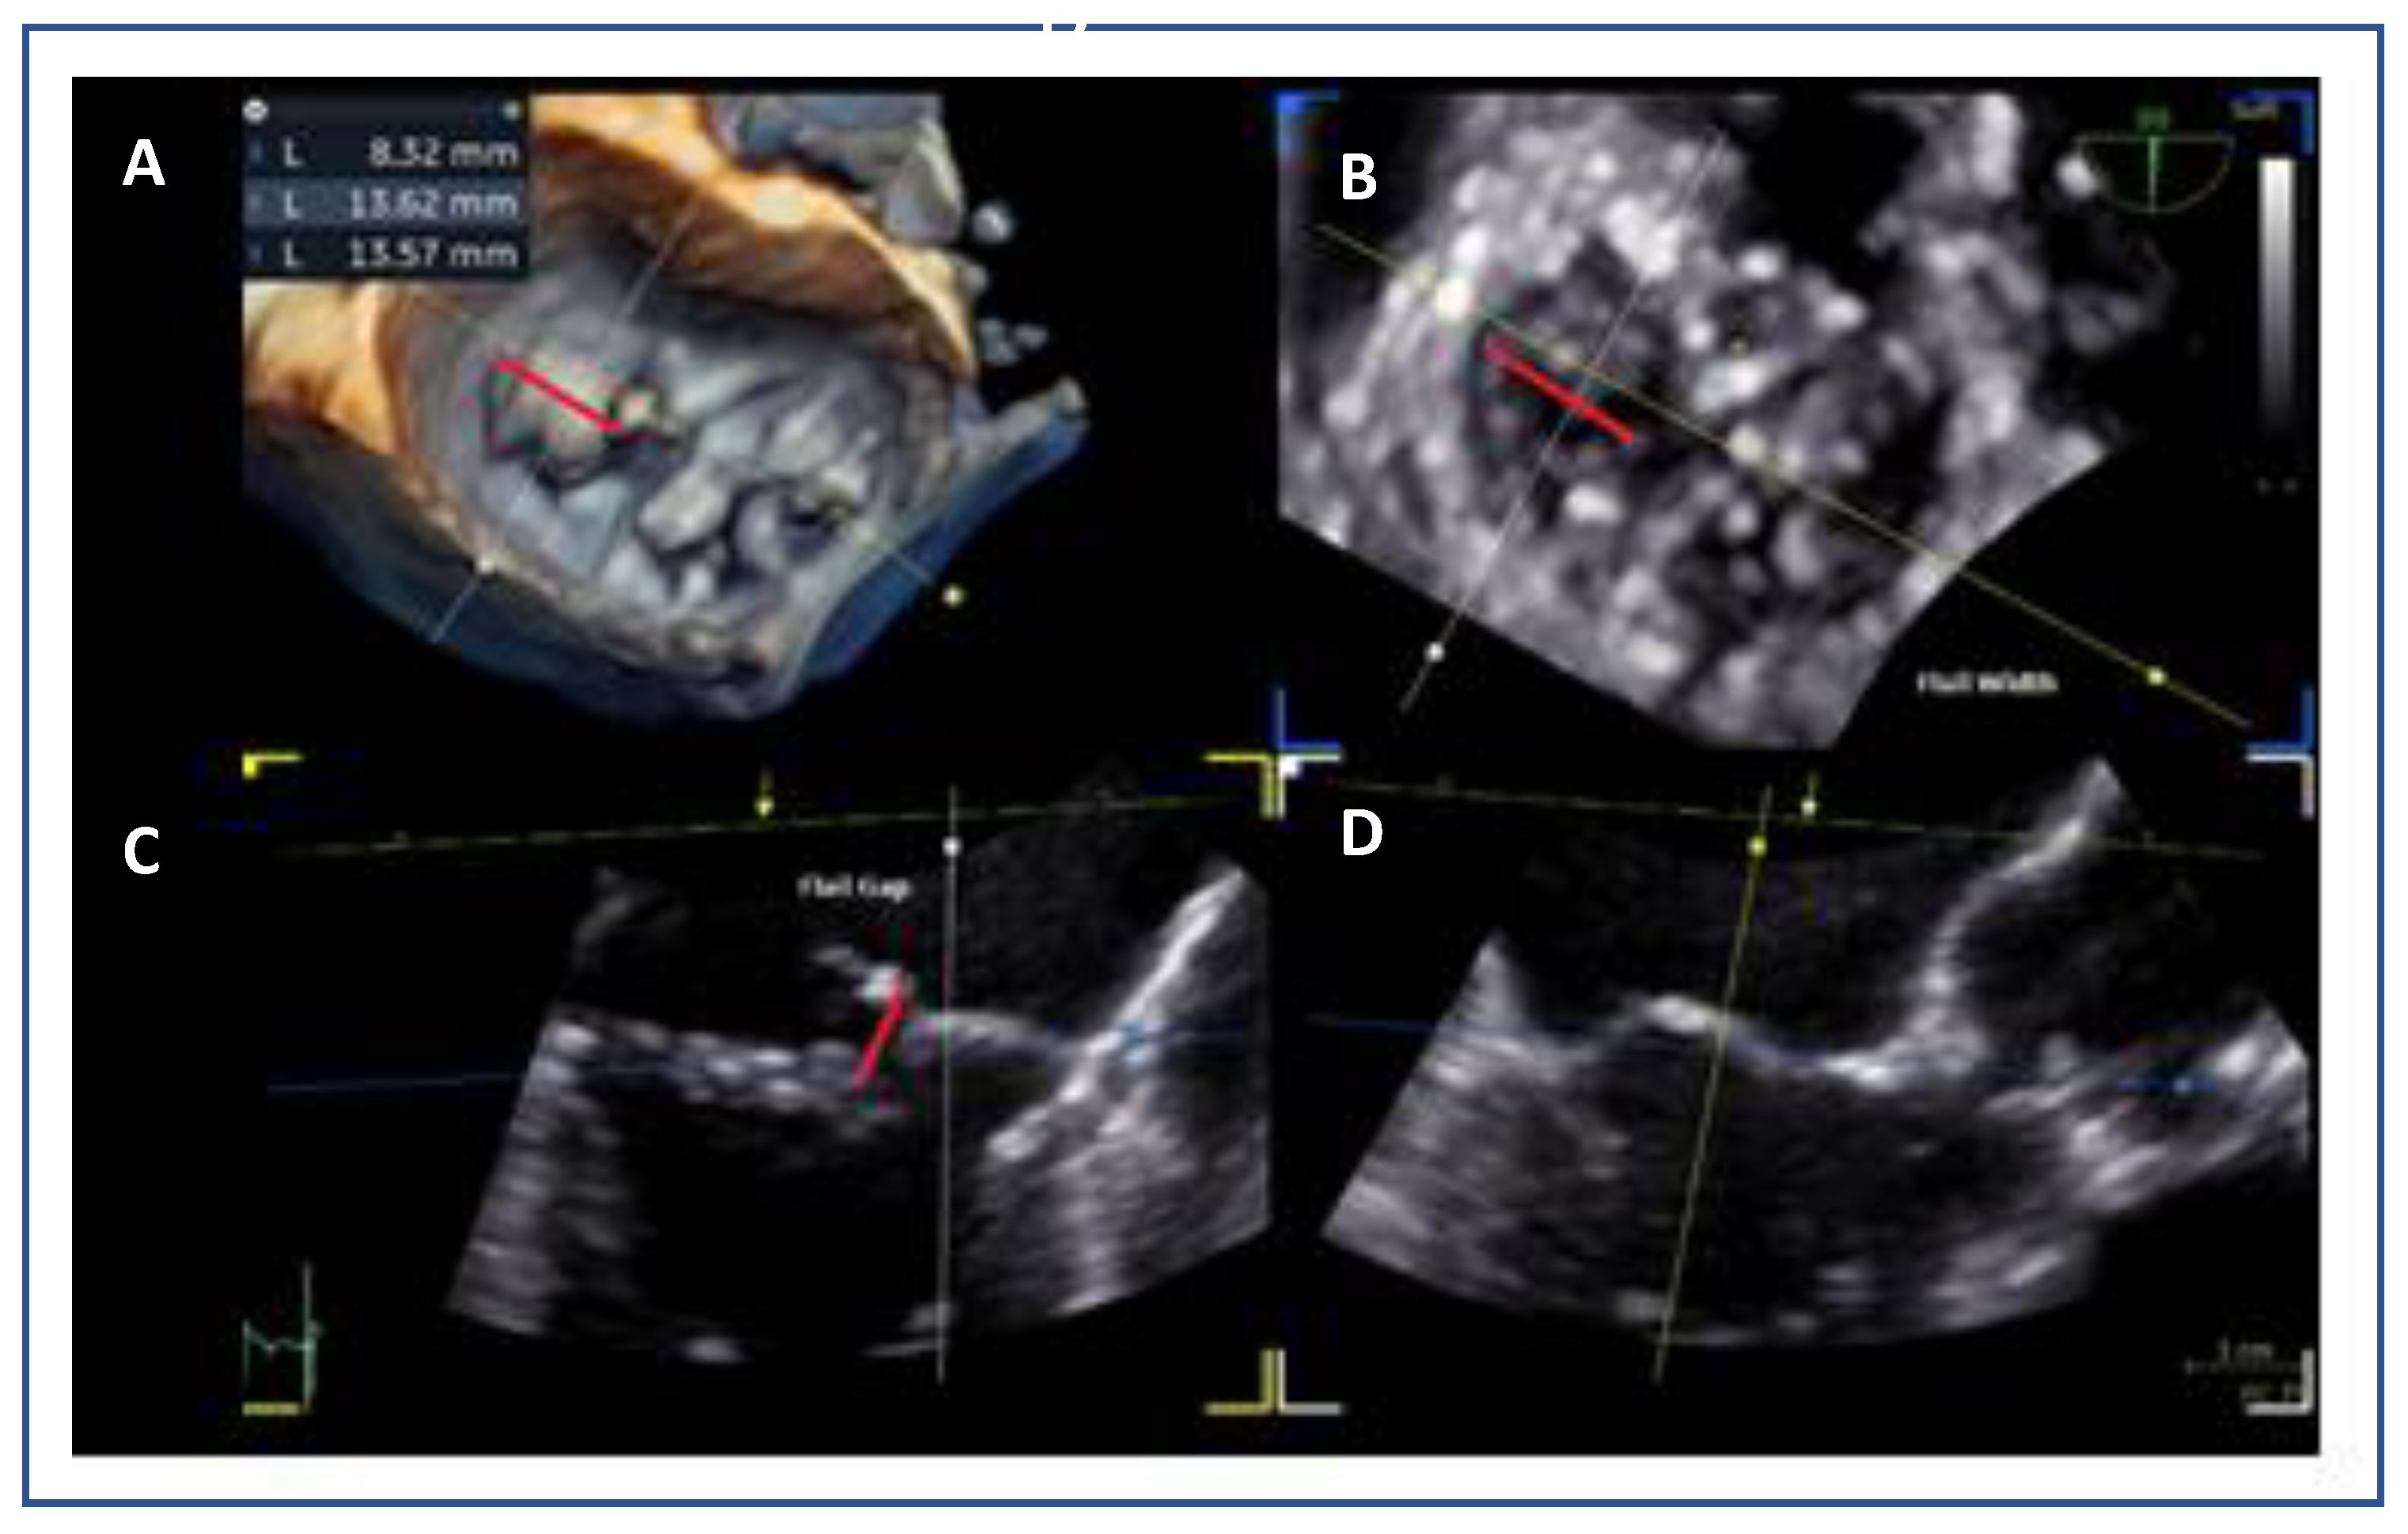

- Flail gap and flail width: Severe primary MR may demonstrate a flail gap >10 mm and width >15 mm, which traditionally limited eligibility, but can be managed in experienced centers.

7.4. Flail Gap and Width (PMR)